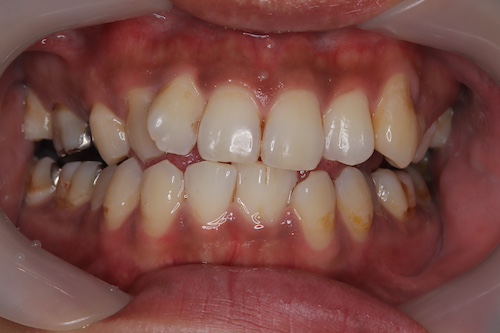

バコ1日20本吸う20代男性クリーニングでステインを除去

20代男性喫煙6年 一日20本、クリーニング希望 ステイン除去希望

1回のクリーニングでのステイン除去、ビフォーアフター写真

一回でここまでステイン取れて嬉しそうにされていた。

ベリーとフロスをお勧めし、購入された。

定期的なクリーニングの必要性をつたえたが、一旦はこれで大丈夫と仰っていた。

喫煙があるのでまたステインつきやすくなると説明しベリー、フロスを毎日使用すること指導した。